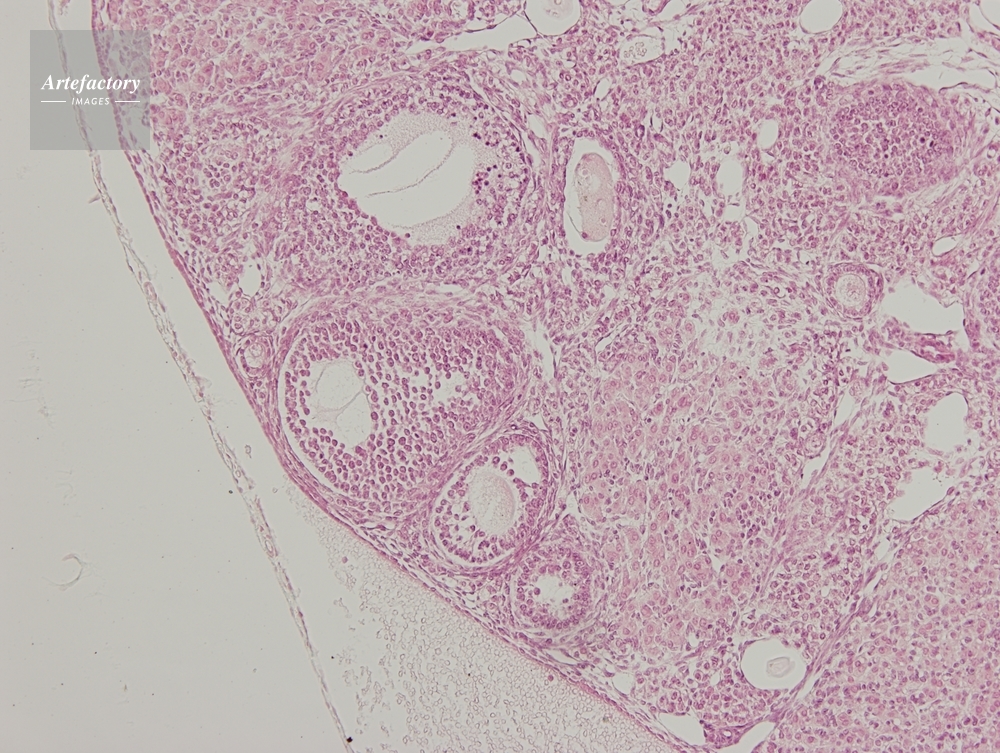

| 作品タイトル | マウス,卵巣 | モデルリリース | なし | |

| 作家 | OLYMPUS CORPORATION Technolab | プロパティリリース | なし | |